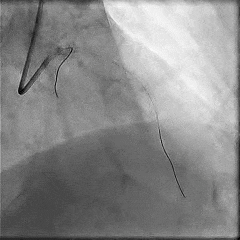

术前冠脉造影:

术前冠脉功能学全面评估:

▶LAD IMR:11;FFR:0.67(+)。

OCT指导下PCI:

术后OCT评估:

PCI术后即刻送入压力导丝复查,测得LAD IMR 27(+),FFR 0.89。血运重建后,该患者LAD FFR值显著升高(0.67→0.89),IMR≥25,需要警惕择期PCI相关的CMD。

术后冠脉造影:

术后即刻冠脉功能学全面评估:

▶LAD IMR:27(+);FFR:0.89。